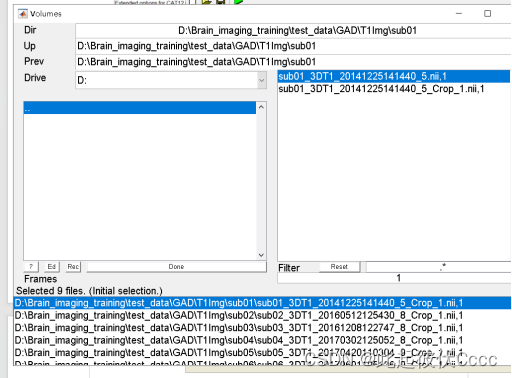

选择需要处理的T1图像,参数配置好后点击左上角的小三角运行即可:

点击后出现如下运行界面: